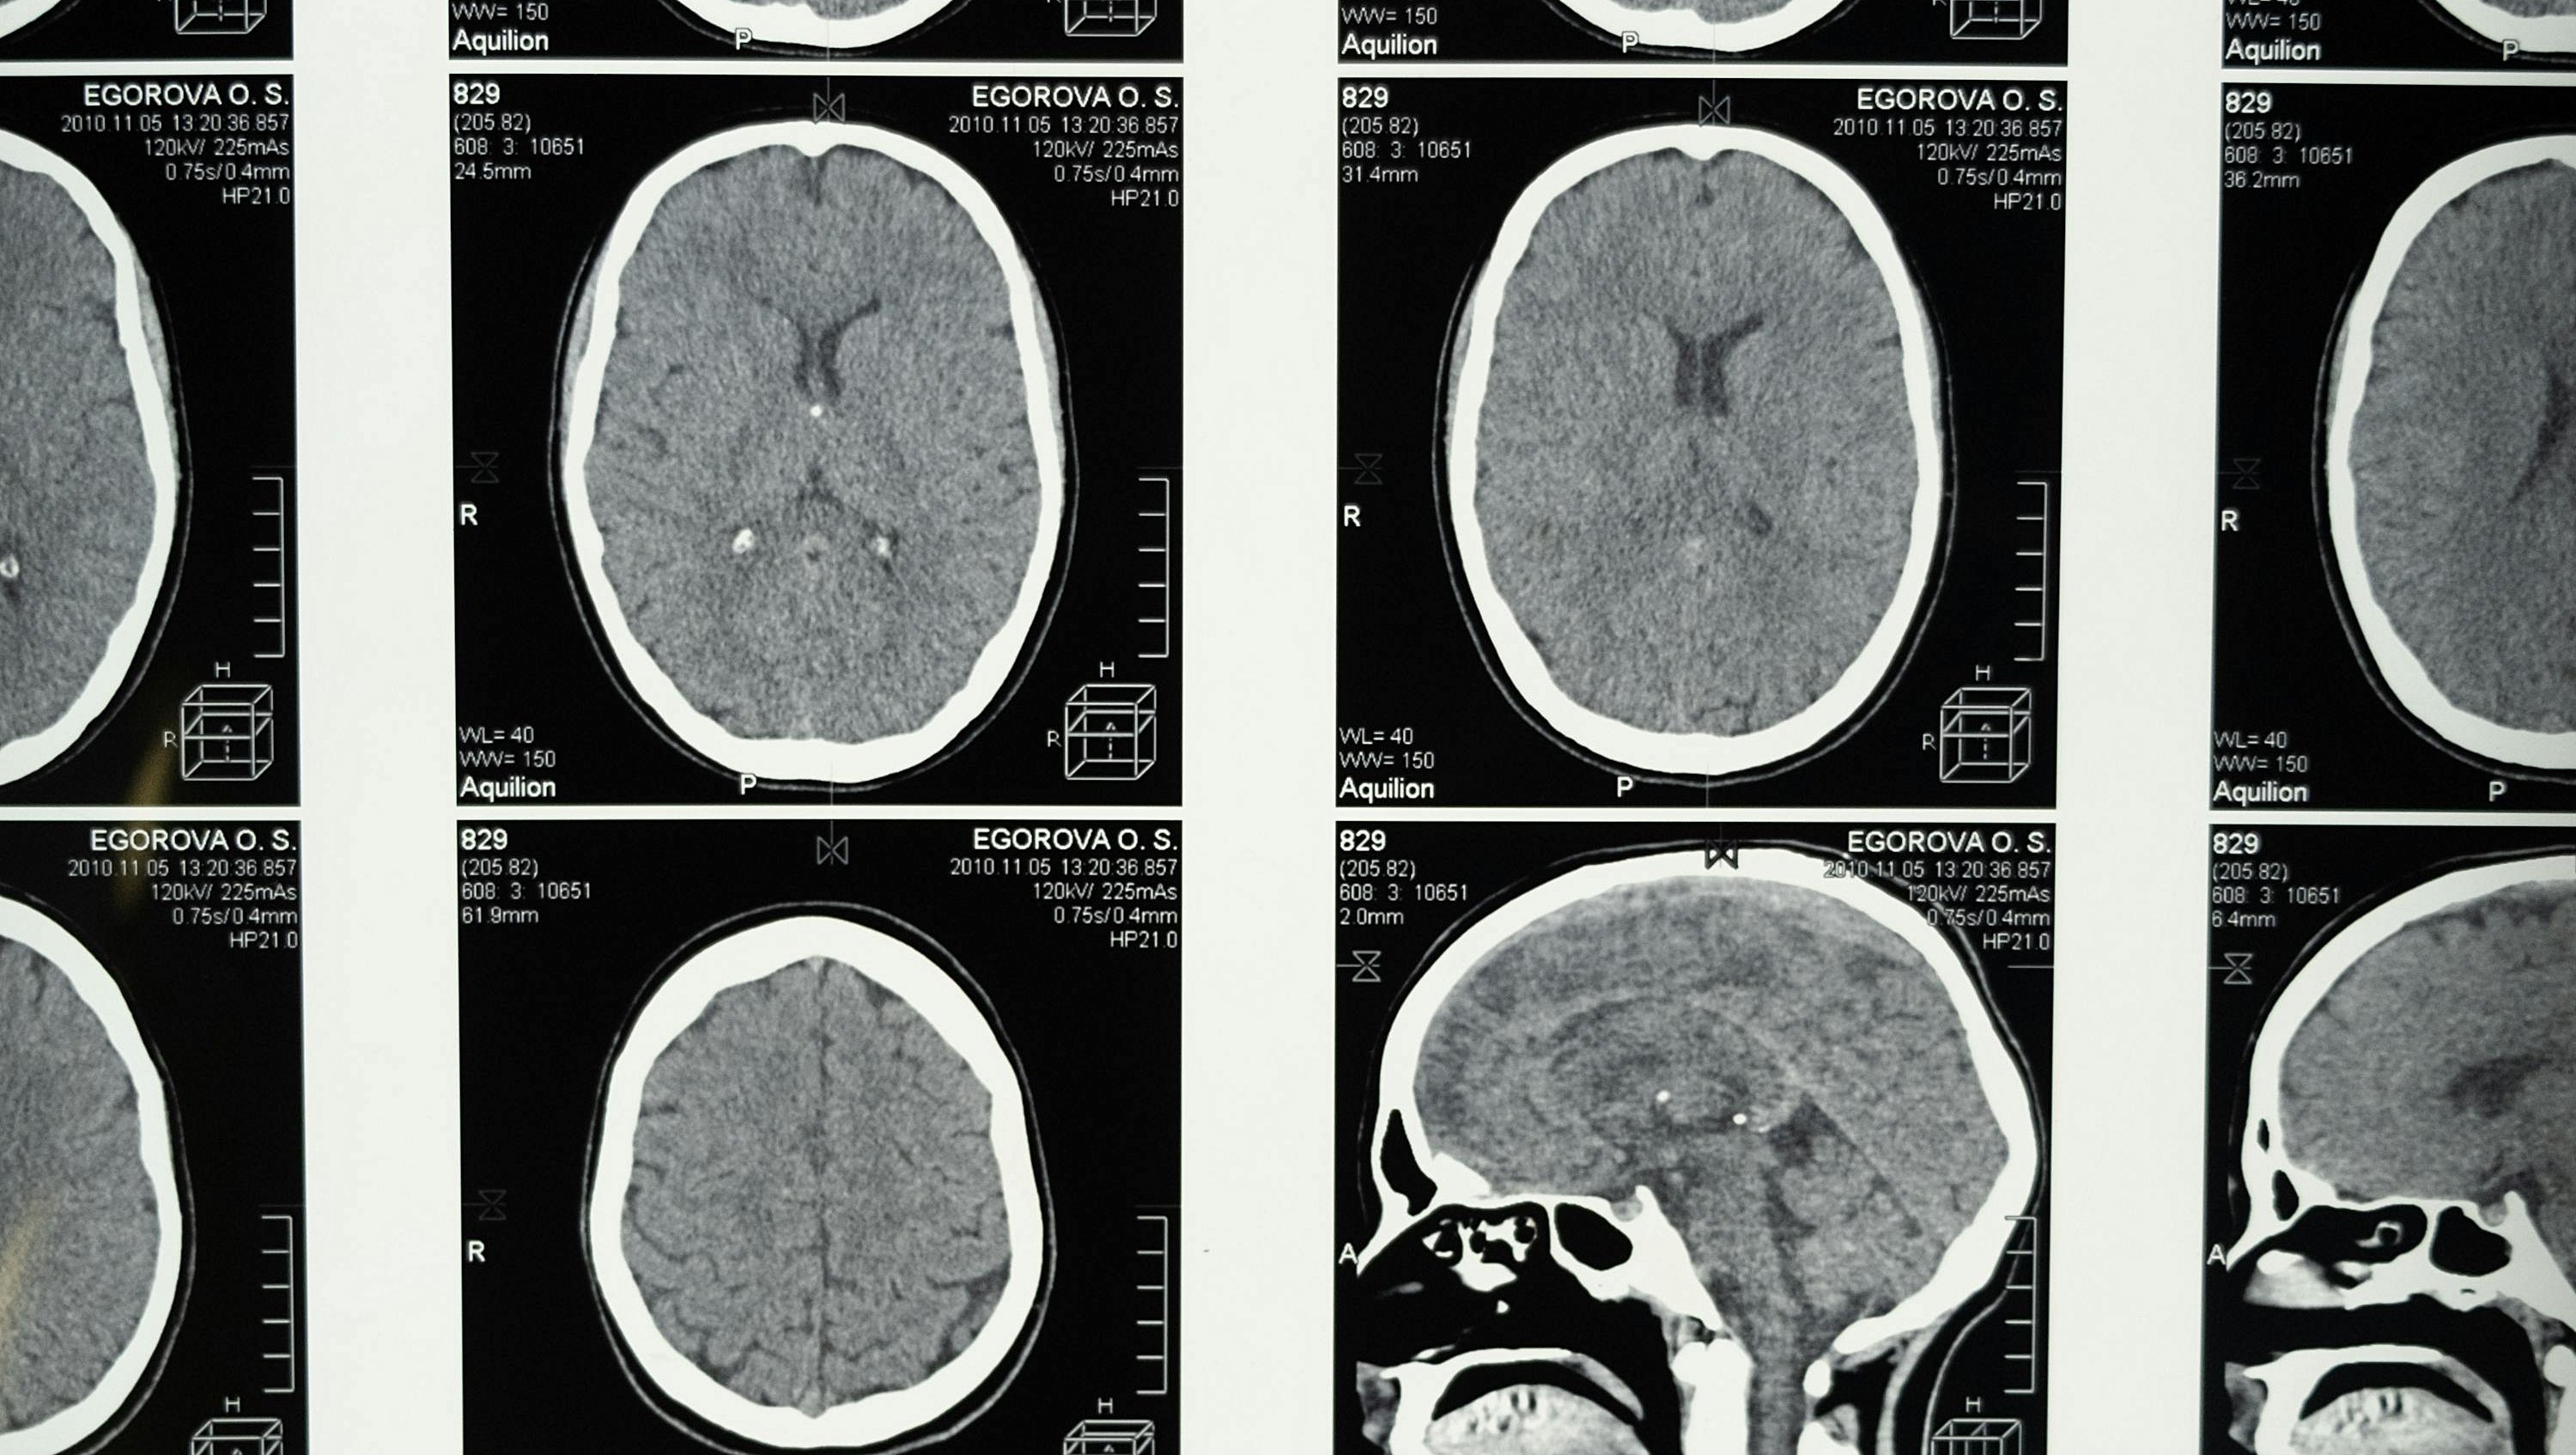

Beyin, insan bedeninin en karmaşık ve en hayati organlarından biridir. Tüm bilinç süreçlerimizi, motor fonksiyonlarımızı ve duygusal tepkilerimizi yöneten bu organ, tarih boyunca sayısız bilimsel araştırmanın odak noktası olmuştur. Ancak, beyin cerrahisinde gerçekleştirilen bazı operasyonlar vardır ki, duyduğunuzda inanması güç gelebilir. Bunlardan en şaşırtıcı olanı, hemispherektomi adı verilen cerrahi işlemdir.

Hemispherektomi, beynin bir yarısının tamamen çıkarılması veya işlevsiz hâle getirilmesini içeren bir ameliyattır. Daha da ilginci, bu operasyonu geçiren bazı hastalar, büyük ölçüde normal yaşamlarını sürdürebilmekte, hatta bilişsel ve motor fonksiyonlarının büyük kısmını koruyabilmektedir. Peki, beynin yarısı olmadan yaşamak nasıl mümkün olabiliyor? Bu makalede, bu olağanüstü cerrahi işlemin arkasındaki bilimsel gerçekleri inceleyeceğiz.

Beynin Yarısı Alındığında Ne Olur?

Beynin iki yarımküresi birbirinden farklı görevler üstlenir. Genellikle sol yarımküre, dili işleme ve mantıklı düşünme becerileriyle ilişkilidirken, sağ yarımküre daha çok uzamsal farkındalık, yaratıcılık ve sezgisel düşünce süreçlerinden sorumludur.